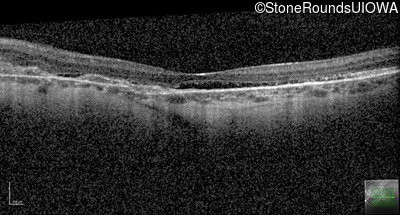

Age at visit: 41 years